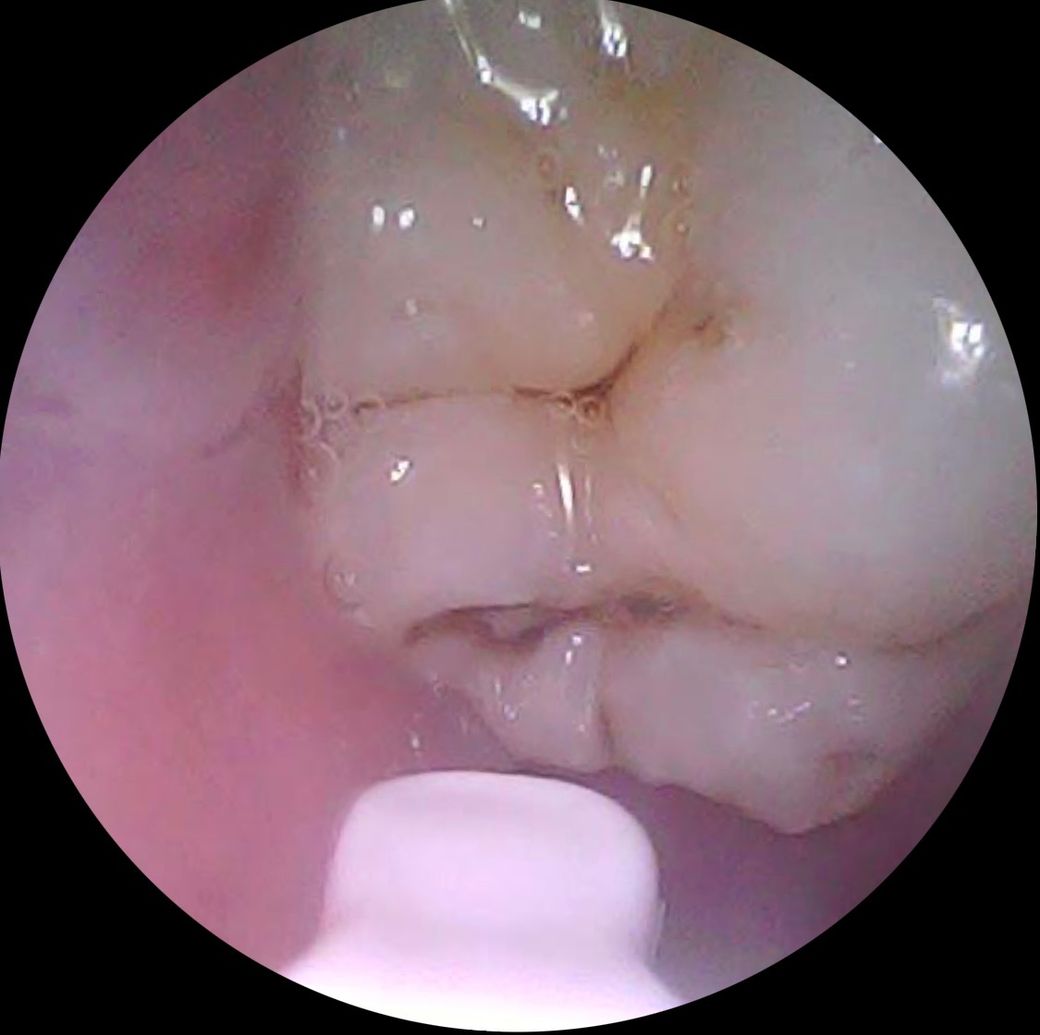

어금니 치아 상태가 어떤지 알려주세요.

1번 사진은 제가 봐도 많이 썩은 거 같아요. 사랑니인데, 곧 뽑으러 갈 예정입니다!

전체 어금니 상태인데, 아래 치아들을 제외하면 깨끗합니다.

전체적으로 보았을 때, 치아 상태가 어떤지 궁금합니다.

충치가 꽤 진행된 부분이 보이기 때문에 치과에서 정확한 검진 후 치료받으셔야할 것 같습니다.

치아에 충치가 있는 것으로 보입니다. 충치에 범위나 정도는 방사선 사진도 같이 있어야 더 정확하게 알 수 있기 때문에 정확한 충치의 범위를 알기 위해서는 치과에서 진료를 받아보는 것이 좋습니다.

엑스레이를 찍어봐야 정확히 알겟지만,첫번째 치아는 충치가 상당히 진행된거 같고 나머지 치아의 충치는 간단한 충치 같습니다.

첫번째 사랑니 제외한다면

2,3,4,6번째는 충치가 그렇게 크진 않습니다 치료가 필요한 정도일지는 엑스레이 찍어봐야합니다

5번째는 치료해야할 것 같습니다